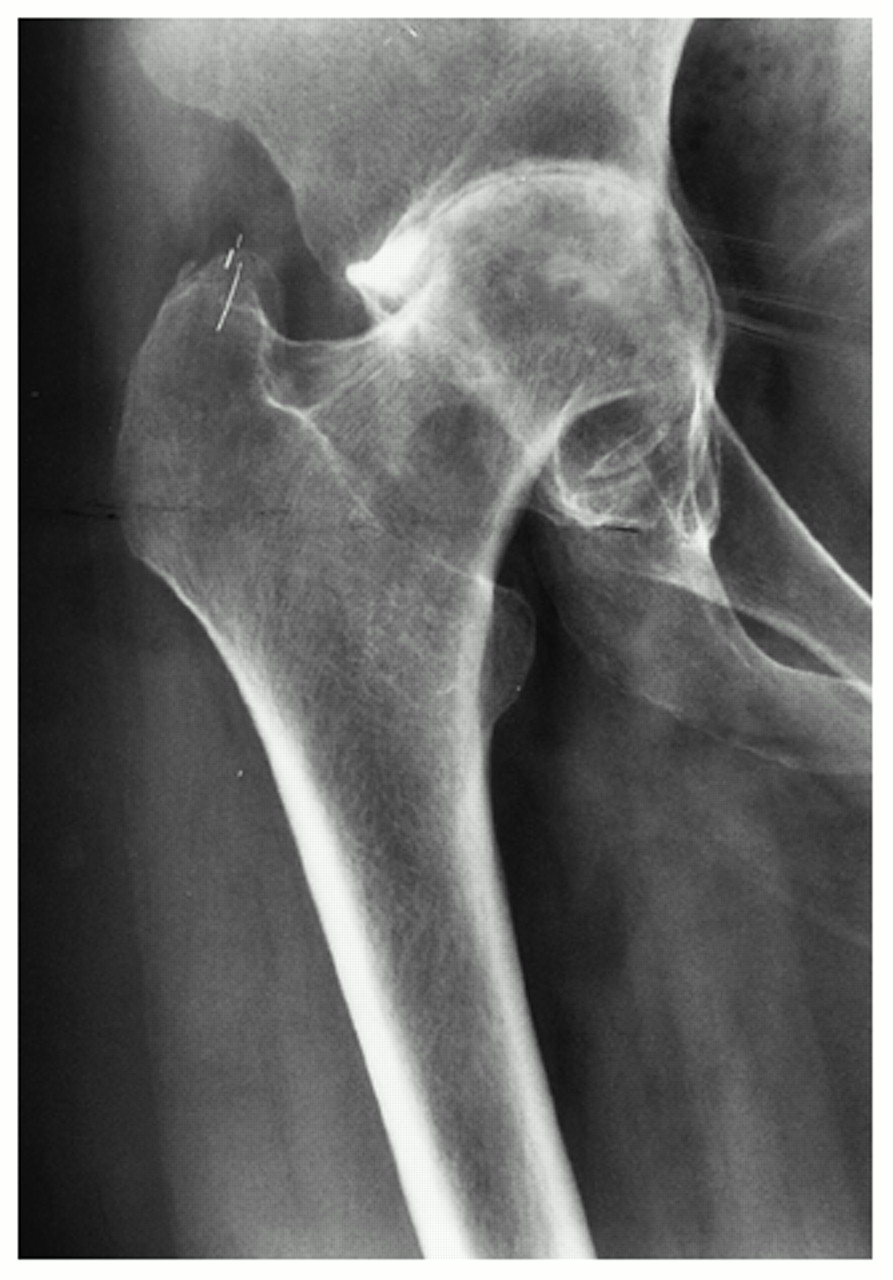

Rheumatic arthritis causes joint erosion and joint destruction visible on x-rays and symptoms that can be severe and limiting. As the joint becomes eroded the cartilage is damaged and the articulation of bone-on-bone causes severe pain. Damage to cartilage, tendons, ligaments and bone causes the hip joint to become deformed and even unstable as rheumatoid arthritis progresses.

The frequency of acetabular protrusio is higher in rheumatoid hips as is the likelihood of significant femoral head deformity. Bone quality is poor especially in those patients who have needed long term steroid treatment. This makes these operations more difficult, with a higher risk of per-operative and post-operative complications.